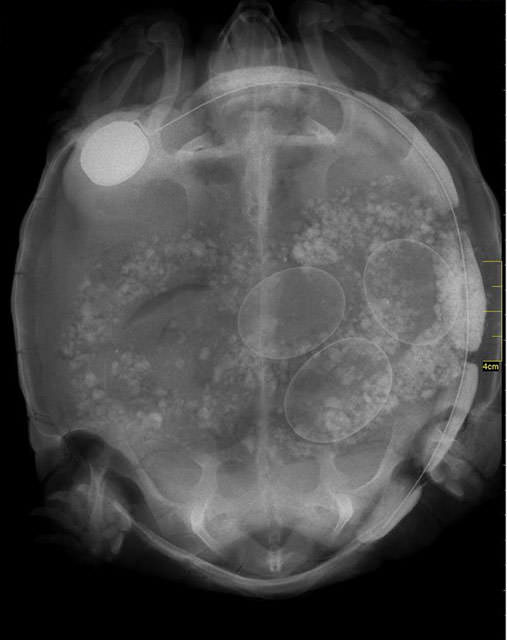

İnsanların ultrason görüntülerini görmeye hepimiz alışkınız. Ancak hamile hayvanların ultrason görüntüleri sizleri çok şaşırtacak.Kaplumbağa

Kaplumbağa